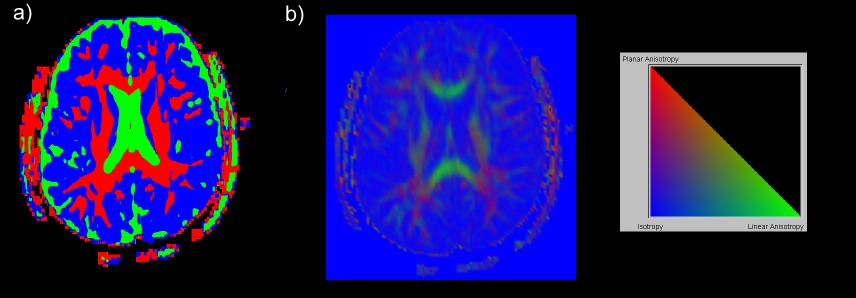

An expression defining a field can also contain conditional statements that can be used to create a segmentation function for different tissue types. Using this tool we can create the visualization shown in part (a) of the figure below. Regions of gray matter, white matter, and Celebral Spinal Fluid are coloured blue, red and green, respectively. Part (b) of the figure shows a slice visualized with a barycentric colour map which uses three interactively derived fields which are positive and add up to one for all points.